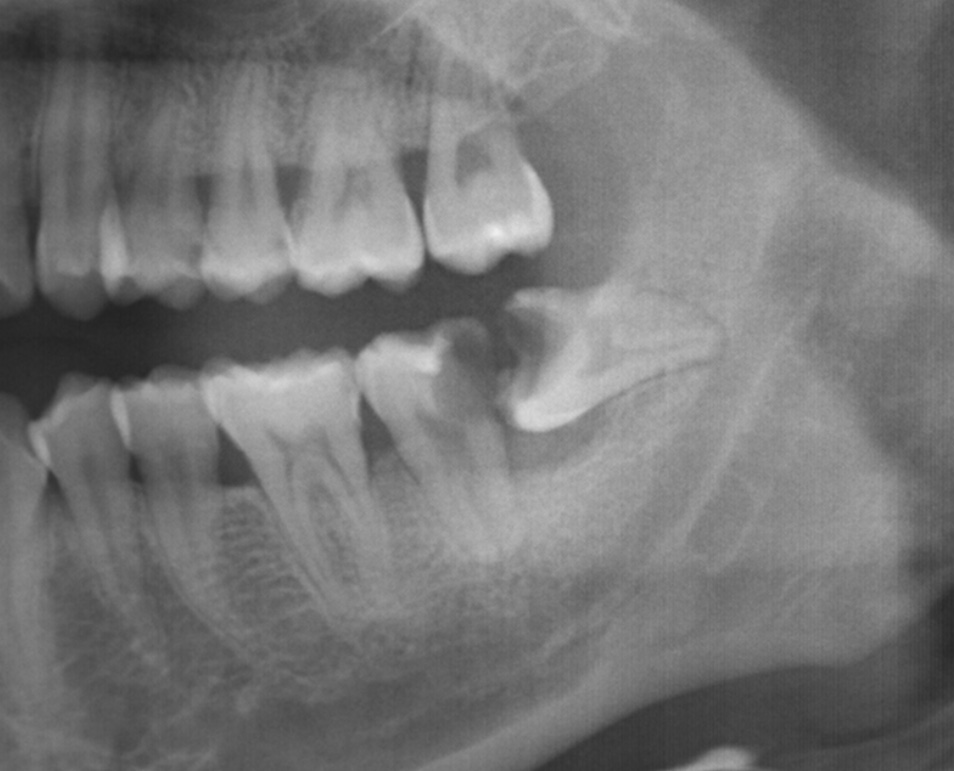

親知らずと口腔外科